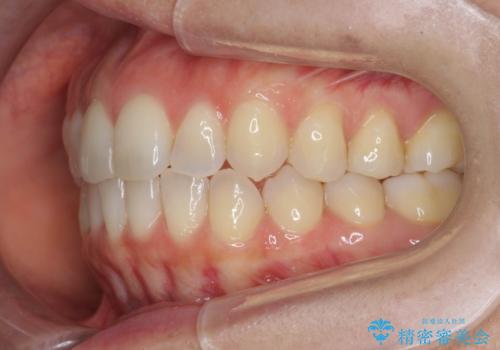

前歯のがたつきをしっかり治すマウスピース矯正

- 前歯のガタガタをきれいに並べたい、と希望され来院されました。

がたつきのないきれいな歯並びに仕上げることができ、満足いただくことができました。